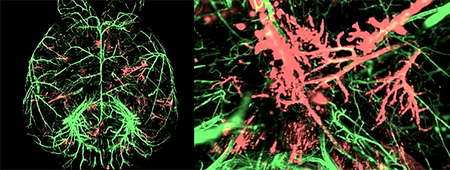

При некоторых типах рака, таких как меланома, для успешного метастазирования в лимфатические узлы и органы необходимо формирование новых лимфатических сосудов в их преметастазной нише. Недавно ученые установили, что такой лимфангиогенез начинается на ранних стадиях роста первичной опухоли, и медиатором его запуска является фактор роста мидкин, секретируемый клетками меланомы в составе экзосом или в свободном виде [19].

Педжет провел аналогию такого распространения раковых клеток с прорастанием семян. Они тоже выживают и делятся на плодотворной «почве» — в подходящем микроокружении. В те времена невозможно было найти этому экспериментального подтверждения, и долго преобладала совсем иная теория — Джеймса Юинга (рис. 2). Он утверждал, что основную роль в распределении метастазов по организму играет динамика кровотока и устройство сосудистой системы.

19. David Olmeda, Daniela Cerezo-Wallis, Erica Riveiro-Falkenbach, Paula C. Pennacchi, Marta Contreras-Alcalde, et. al.. (2017). Whole-body imaging of lymphovascular niches identifies pre-metastatic roles of midkine. Nature. 546, 676-680;